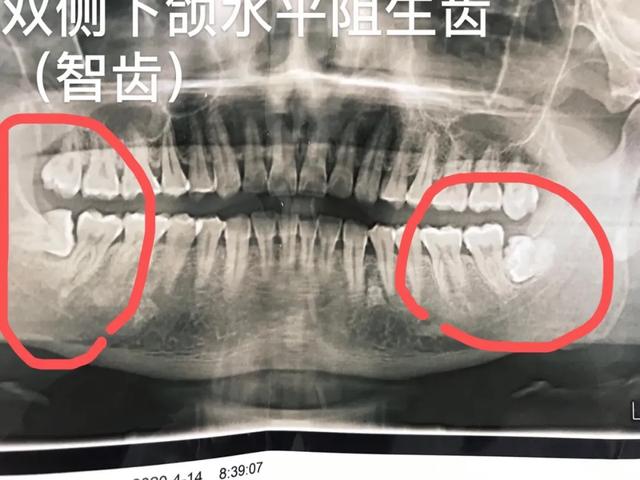

女同胞怀孕是人生中非常重要的时期。孩子和母亲都需要特殊保护。在这个时期,他们的身体抵抗力较低,一些平时很容易生病的疾病,尤其是牙病,对疼痛难以忍受,治疗起来非常麻烦,需要多次治疗。口腔科用的药物很多。虽然理论上治疗问题不大,但实际上大多数患者都不愿意为孩子冒险。所以女性同胞最好先解决牙齿问题,尤其是孕前的智齿问题。

怀孕期间,由于体内雌激素水平升高,牙龈非常容易出血。如果不注意口腔卫生,牙龈会增生肿胀,严重出血,严重影响正常生活。由于身体抵抗力低,智齿冠周炎的发病率极高。此时患者会出现牙龈肿胀、面部肿胀、颌下淋巴结肿大、严重张口发热等情况,影响正常生活。

怀孕期间最好也不要拔牙,因为可能会用到消炎止痛的药物。会影响宝宝。因此,最好在怀孕前治疗牙齿,否则,当你的牙齿疼痛时,你不能吃药或治疗你的牙齿。因为有些牙病可能需要拍X线片,这种情况下需要缓解X线辐射,在拔牙的情况下存在使用麻醉剂的问题。对于这个问题,最好选择间隔2-3个月再考虑怀孕。

口腔医学教科书明确指出,拔牙不适合怀孕前三个月和后三个月,很可能导致流产和早产。事实上,因为患者害怕牙科治疗,即使在妊娠中期,即使进行其他手术而不是拔牙,也很难保证不会出现问题。一旦出现问题,医生和患者都会留下终身遗憾,所以很多患者选择耐心,很多医生拒绝治疗患者也是可以理解的。

4.微创拔除各类阻生牙(智齿)、儿童埋伏牙、复杂牙等疑难牙。治疗效果显著。